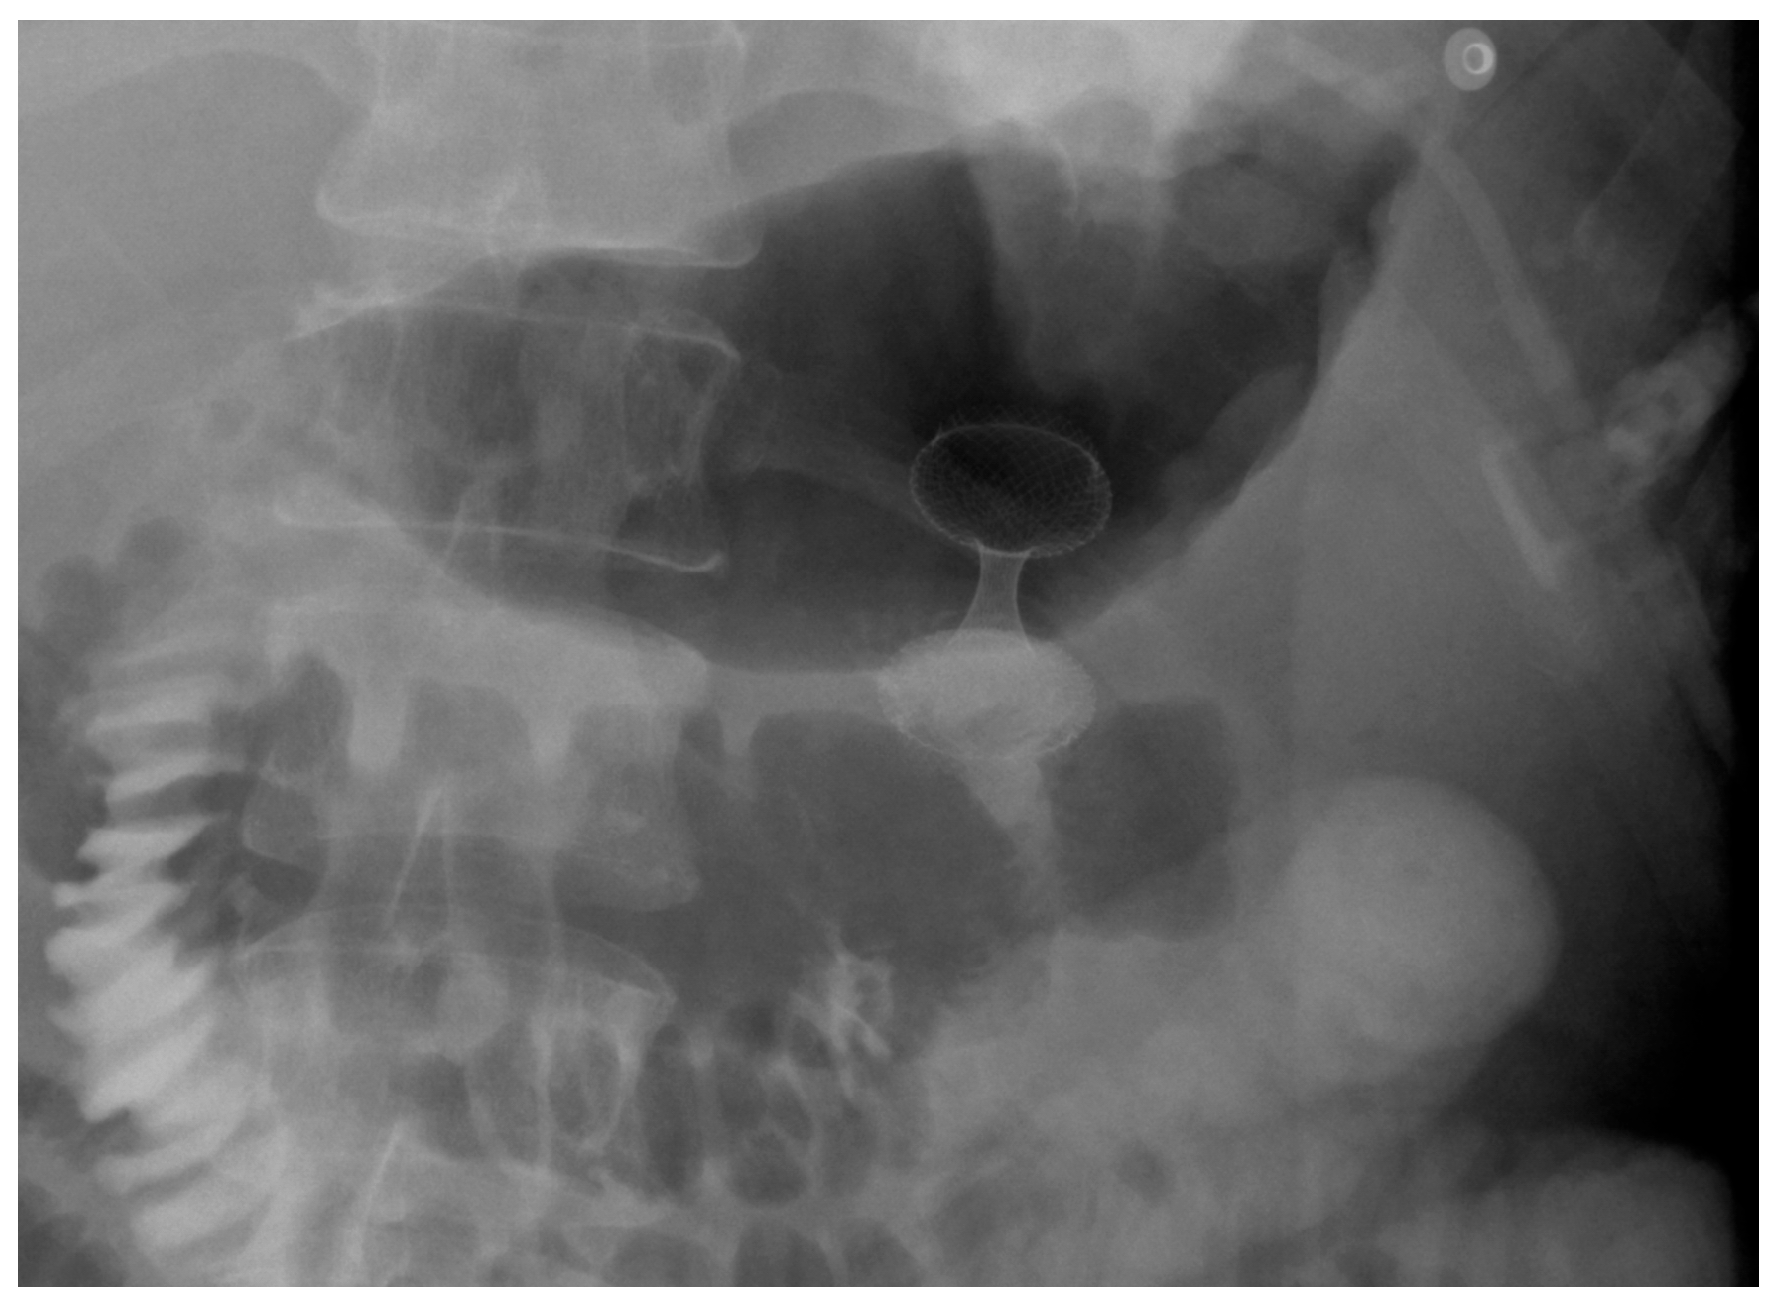

4. Gastroduodenal Tract—Gastric Outlet Obstruction

4.1. Malignant GOO

4.1.1. Role of Stent

Indications and Mechanism of Action